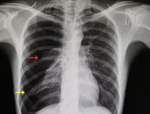

1. A 37-year-old man, with no known medical illness, came for a routine medical check-up. His chest radiograph is presented to you. Identify the incorrect statement with respect to the X-ray shown below.

1. The structure marked as number 2 is right ventricular border

2. The structure marked as 1 is the trachea

3. The structure marked as 3 is the left ventricular border

4. The structure marked as 4 is the aortic arch